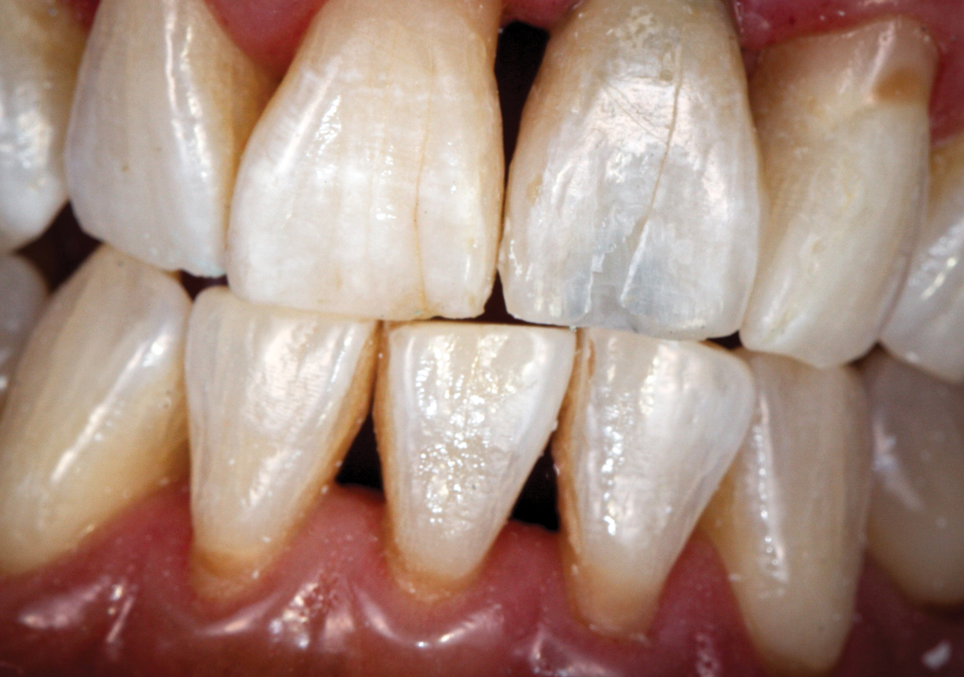

To demonstrate the principles and protocols described in this article, three case examples are included. The first case involves the treatment of a patient who sought replacement of the maxillary left canine (tooth No. 11) with an implant-supported restoration (Figure 11 through Figure 34), and in the second case, the patient presented for replacement of the maxillary left central incisor (tooth No. 9) (Figure 35 through Figure 44). In the third case, the patient also presented for replacement of the maxillary left central incisor (tooth No. 9) but had a preexisting bonded pontic made from the natural tooth. This was utilized in lieu of a composite tooth shell to fabricate the immediate provisional restoration. (Figure 45 through Figure 57).

(45.) A patient presented for the replacement of the maxillary left central incisor with a bonded pontic made from the natural tooth, which was removed.

Figure 45